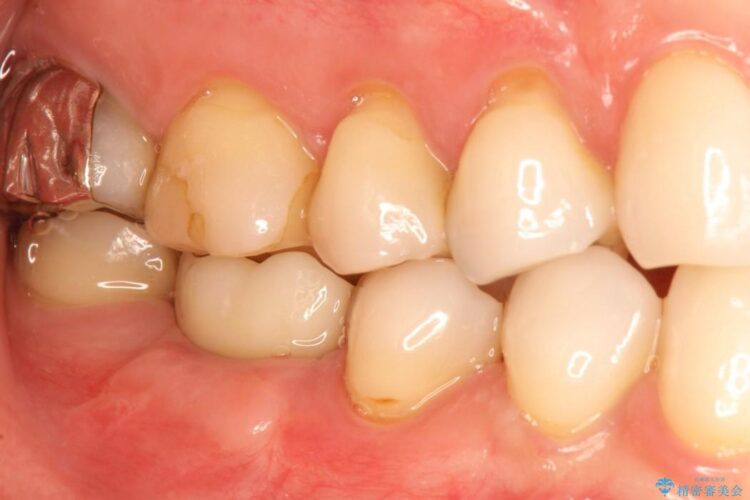

精密な検査を行ったところ、根が完全に折れている為、抜歯が必要となりました。抜歯後は骨と歯茎が痩せてしまう事がないように、人工の骨をつめ、インプラント治療を行う計画としました。

抜歯を行った当日に骨の維持をする為、人工の骨を充填しました。インプラントを埋入する際には、ほとんどが自分の骨に置き換わっており、頬舌的なへこみを引き起こす事もなく、審美性・機能性ともに維持する事が出来ました。

また今回の治療では「バイコンインプラント」を使用する事により、インプラントの土台とセラミッククラウンを付ける際にセメントが全く残らないという利点を生かしたところ、見た目にも綺麗に仕上がり、患者様にも喜んでいただきました。